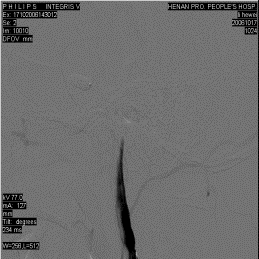

外傷後頸內動脈閉塞右側頸內動脈DSA側位動脈期

診斷:對輕型腦損傷伴有頸內動脈閉塞的病人,常能從臨床表現與腦損傷程度不符而疑及此症,特別是傷後1~2天病情突然加重出現大腦半球缺血的徵象,如嗜睡、偏癱、偏身感覺障礙、患側眼黑矇或失語等症狀。若同時伴有一側頸動脈搏動減弱或消失,病側眼底動脈壓下降、蒼白變細或視網膜染色遲緩即應考慮本病。對重型腦損傷伴有頸內動脈閉塞的病人,要在腦缺血尚未至不可逆損害之前就明確診斷,並非易事,只有在密切觀察的前提下,及時採用影像學輔助檢查,才能作出早期診斷。腦血管造影檢查可以直接顯示動脈閉塞的具體部位和程度,有助於治療的抉擇可謂最有價值的診斷方法。CT和MRI檢查有助於診斷。

1、腦血管造影可見患側頸內動脈顱外段阻塞,大腦中與大腦前動脈影像消失。